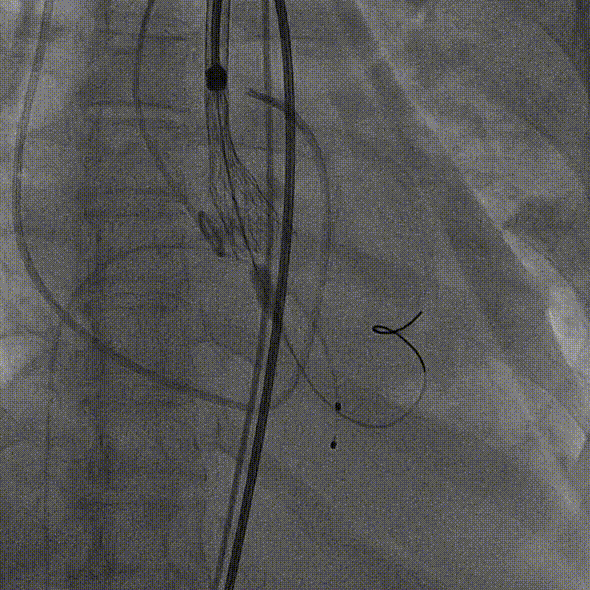

3.TaurusElite AV26号瓣膜定位及释放。瓣膜初始定位瓣下2mm,开花后120次起搏,释放到工作位后造影显示锚定充足,位置良好,冠脉未见遮挡,继续缓慢旋转手柄,瓣膜逐一脱钩,顺利释放。

瓣膜初始定位

瓣膜释放过程

瓣膜脱钩